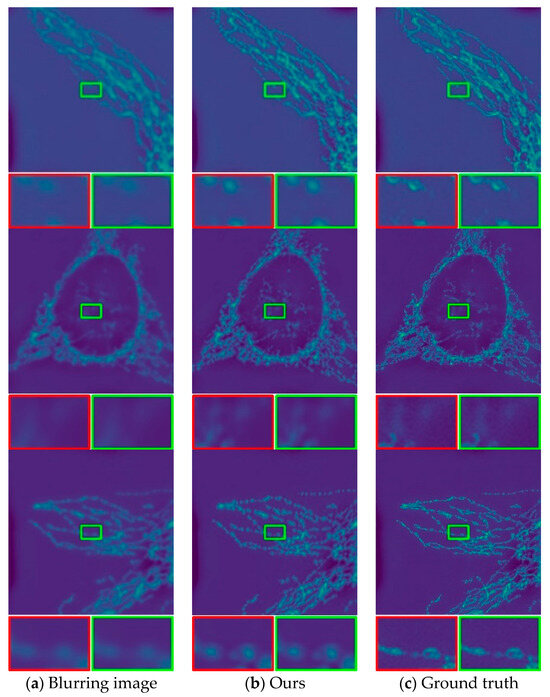

3.3. Evaluation on the Image Deblurring Network

3.4. Evaluate the Deblurring Effect on Real pCLE Images